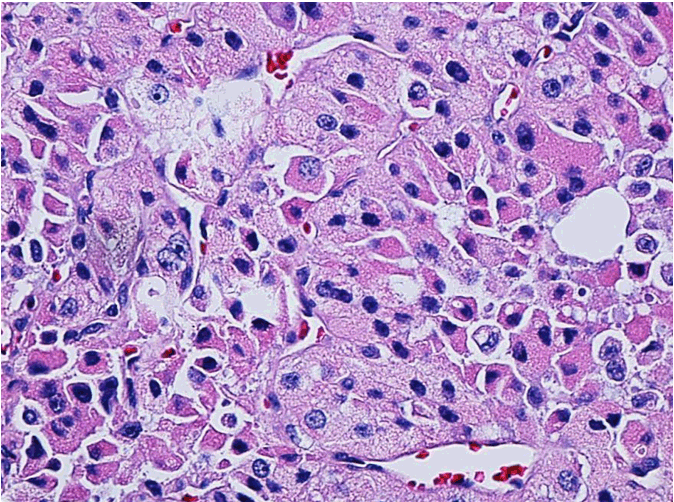

Figure 1: Hurthle cell Carcinoma: large cell with abundant granular eosinophilic cytoplasm with round nucleus and prominent nucleolus (H&E, high power).